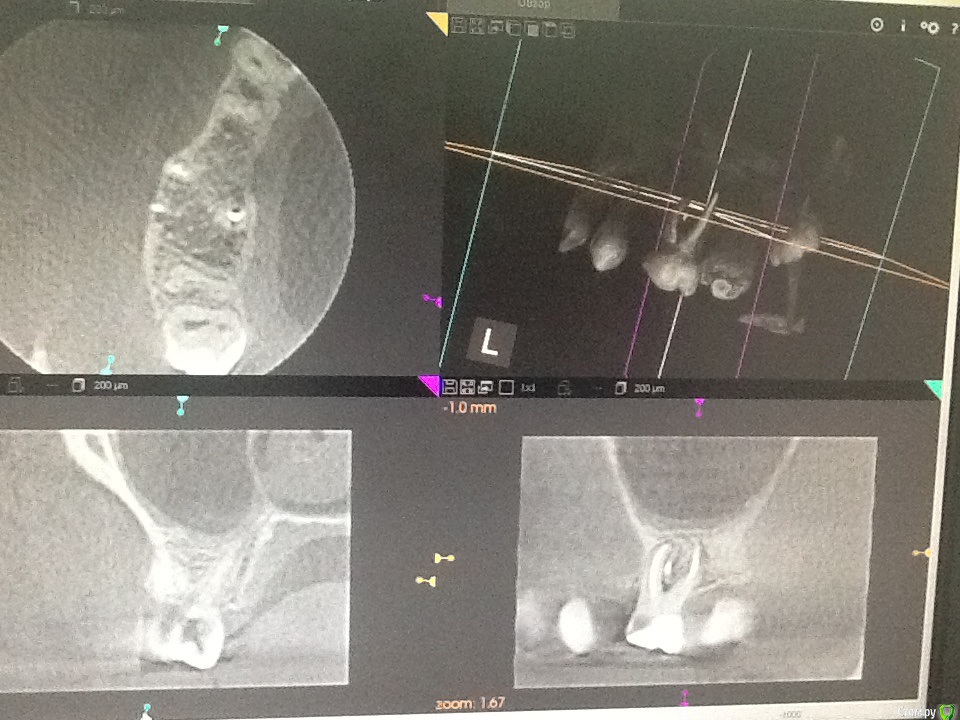

Л Ю С Я Опубликовано 25 ноября, 2015 Поделиться Опубликовано 25 ноября, 2015 (изменено) После удачного эндо ( если причина в этом) в пазухе все будет хорошо. Полечили пульпит , через 6 месяцев прислали от лориков с подозрением на одонтогенныйЧерез 6 месяцев после перелечивания Изменено 25 ноября, 2015 пользователем Л Ю С Я 1 Ссылка на комментарий

Сева северный Опубликовано 25 ноября, 2015 Поделиться Опубликовано 25 ноября, 2015 После удачного эндо ( если причина в этом) в пазухе все будет хорошо. Полечили пульпит , через 6 месяцев прислали от лориков с подозрением на одонтогенныйimage.jpegimage.jpegЧерез 6 месяцев после перелечиванияimage.jpegimage.jpegДа показательно..... У меня с одонтогенными ЛОР проблемми чаще вот так.. Ссылка на комментарий

Сева северный Опубликовано 25 ноября, 2015 Поделиться Опубликовано 25 ноября, 2015 (изменено) Этот зуб будет мучить пациента если эндо проведено неудачно, не получилось, не удалось и т д. Если с эндо все в порядке, на реколле положительная динамика, я вот уверена, что там срок службы больше 10 лет, при условии изготовления хорошей коронки . Если не сложно, ответьте , пожалуйста , через сколько после удаления сделан снимок, здесь явно не через 2 неделиПовторное Кт было сделано через 6 месяцев.. Для сохранения обьемов кости, удаление было сделано с костной пластикой. Сейчас, предстоит имплантация. терапевт...хирург и ортопед .на один и тот же зуб смотрит по разному...Это данность.Это как в анекдоте... Когда родители заходят в комнату где их сын занимается любовью с девушкой. мысли вслух всех четверыхПарень: Ну все застукали...Девушка: Теперь он точно на мне женится..Мать: Ну как он закинул ногу.... ему же так неудобно..Отец: Да ..вырос сынок... пора покупать мотоцикл. Изменено 25 ноября, 2015 пользователем Сева северный Ссылка на комментарий

Л Ю С Я Опубликовано 25 ноября, 2015 Поделиться Опубликовано 25 ноября, 2015 Повторное Кт было сделано через 6 месяцев.. Для сохранения обьемов кости, удаление было сделано с костной пластикой. Сейчас, предстоит имплантация. терапевт...хирург и ортопед .на один и тот же зуб смотрит по разному...Это данность.Может быть и так. Но должны быть положительные результаты. Когда я показываю свои результаты эндо после 2,4 лет наблюдения хирургам, которые были категорически против лечения, доводы такие: нуачерез 10 лет? А Вы можете гарантировать , что не будет переимплантита через 10 лет? 1 Ссылка на комментарий